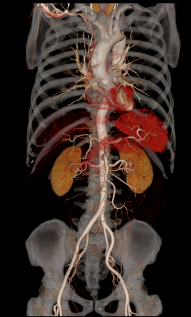

Chẩn đoán hình ảnh mô mềm tiên tiến cho vùng bụng.

Tăng cường độ tương phản I-ốt.

Hỗ trợ đánh giá an toàn cho bệnh nhân.

Đảm bảo hình ảnh chất lượng cao.